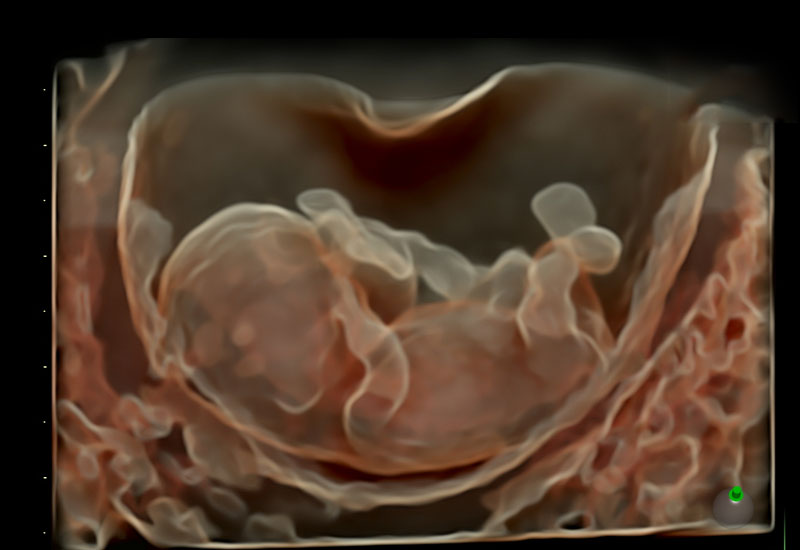

Early Pregnancy Scan

The Early Pregnancy Scan is an important ultrasound examination performed in the first few weeks of pregnancy. It provides reliable confirmation of pregnancy, ensures the baby is developing in the correct location, and helps establish accurate dates. Under the expertise of Dr. Ashwini Rathi, this scan offers both medical reassurance and emotional comfort during the earliest stages of pregnancy.

The Early Pregnancy Scan is usually performed between 6 to 9 weeks of pregnancy. At this stage, important structures like the gestational sac, yolk sac, and fetal heartbeat can be clearly seen.

The scan may be performed either abdominally or by a transvaginal approach, depending on the stage of pregnancy and visibility. The transvaginal scan provides clearer images in very early pregnancy and is safe for both mother and baby.

At this early stage, the main focus is on confirming a healthy, viable pregnancy. Structural abnormalities are usually not assessed at this time and are evaluated later at the nuchal translucency scan and anomaly scan.

However, early indicators of abnormal pregnancy, threatened miscarriage, or ectopic pregnancy can often be detected.